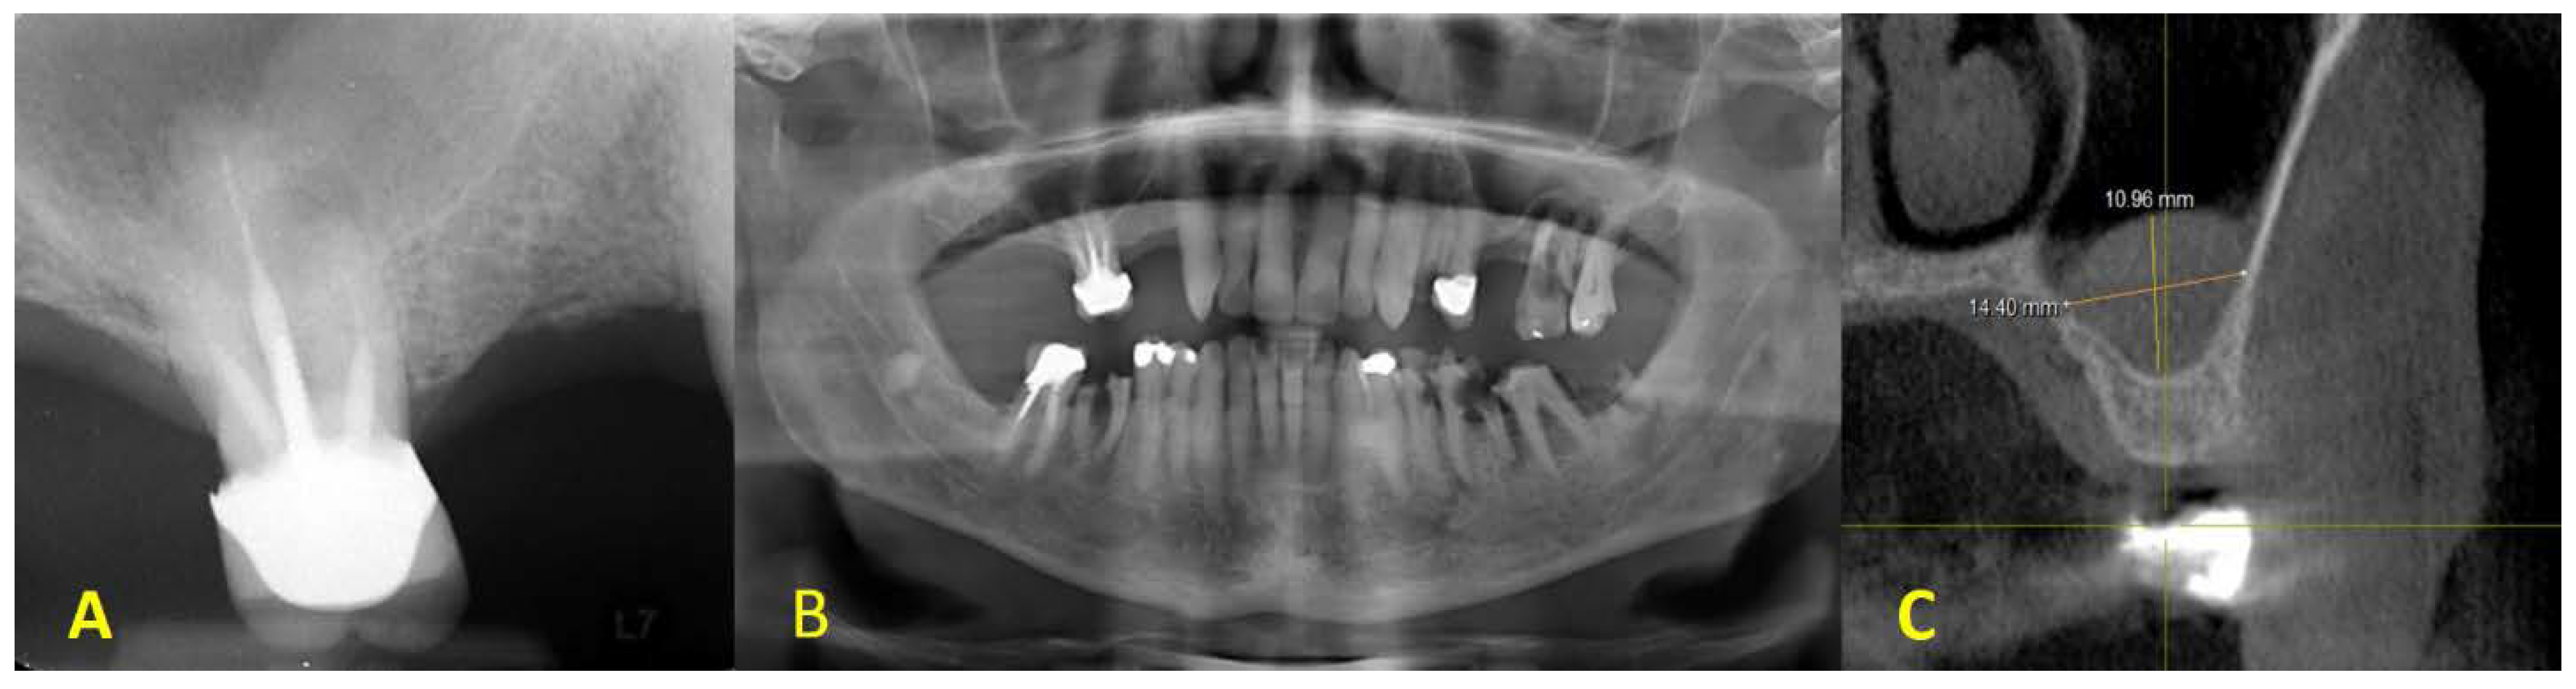

2. Clinical Presentation